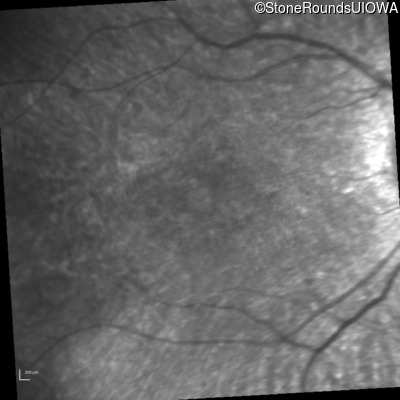

Infrared Fundus Photograph - Right - 20/80 -1

Exemplar